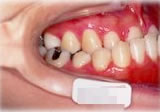

反対咬合(受け口)症例

初診時年齢24歳6ヶ月。前歯部反対咬合を主訴に来院。

骨格性反対咬合と診断し、外科的処置を併用して治療。

右側面 右側面 右側面